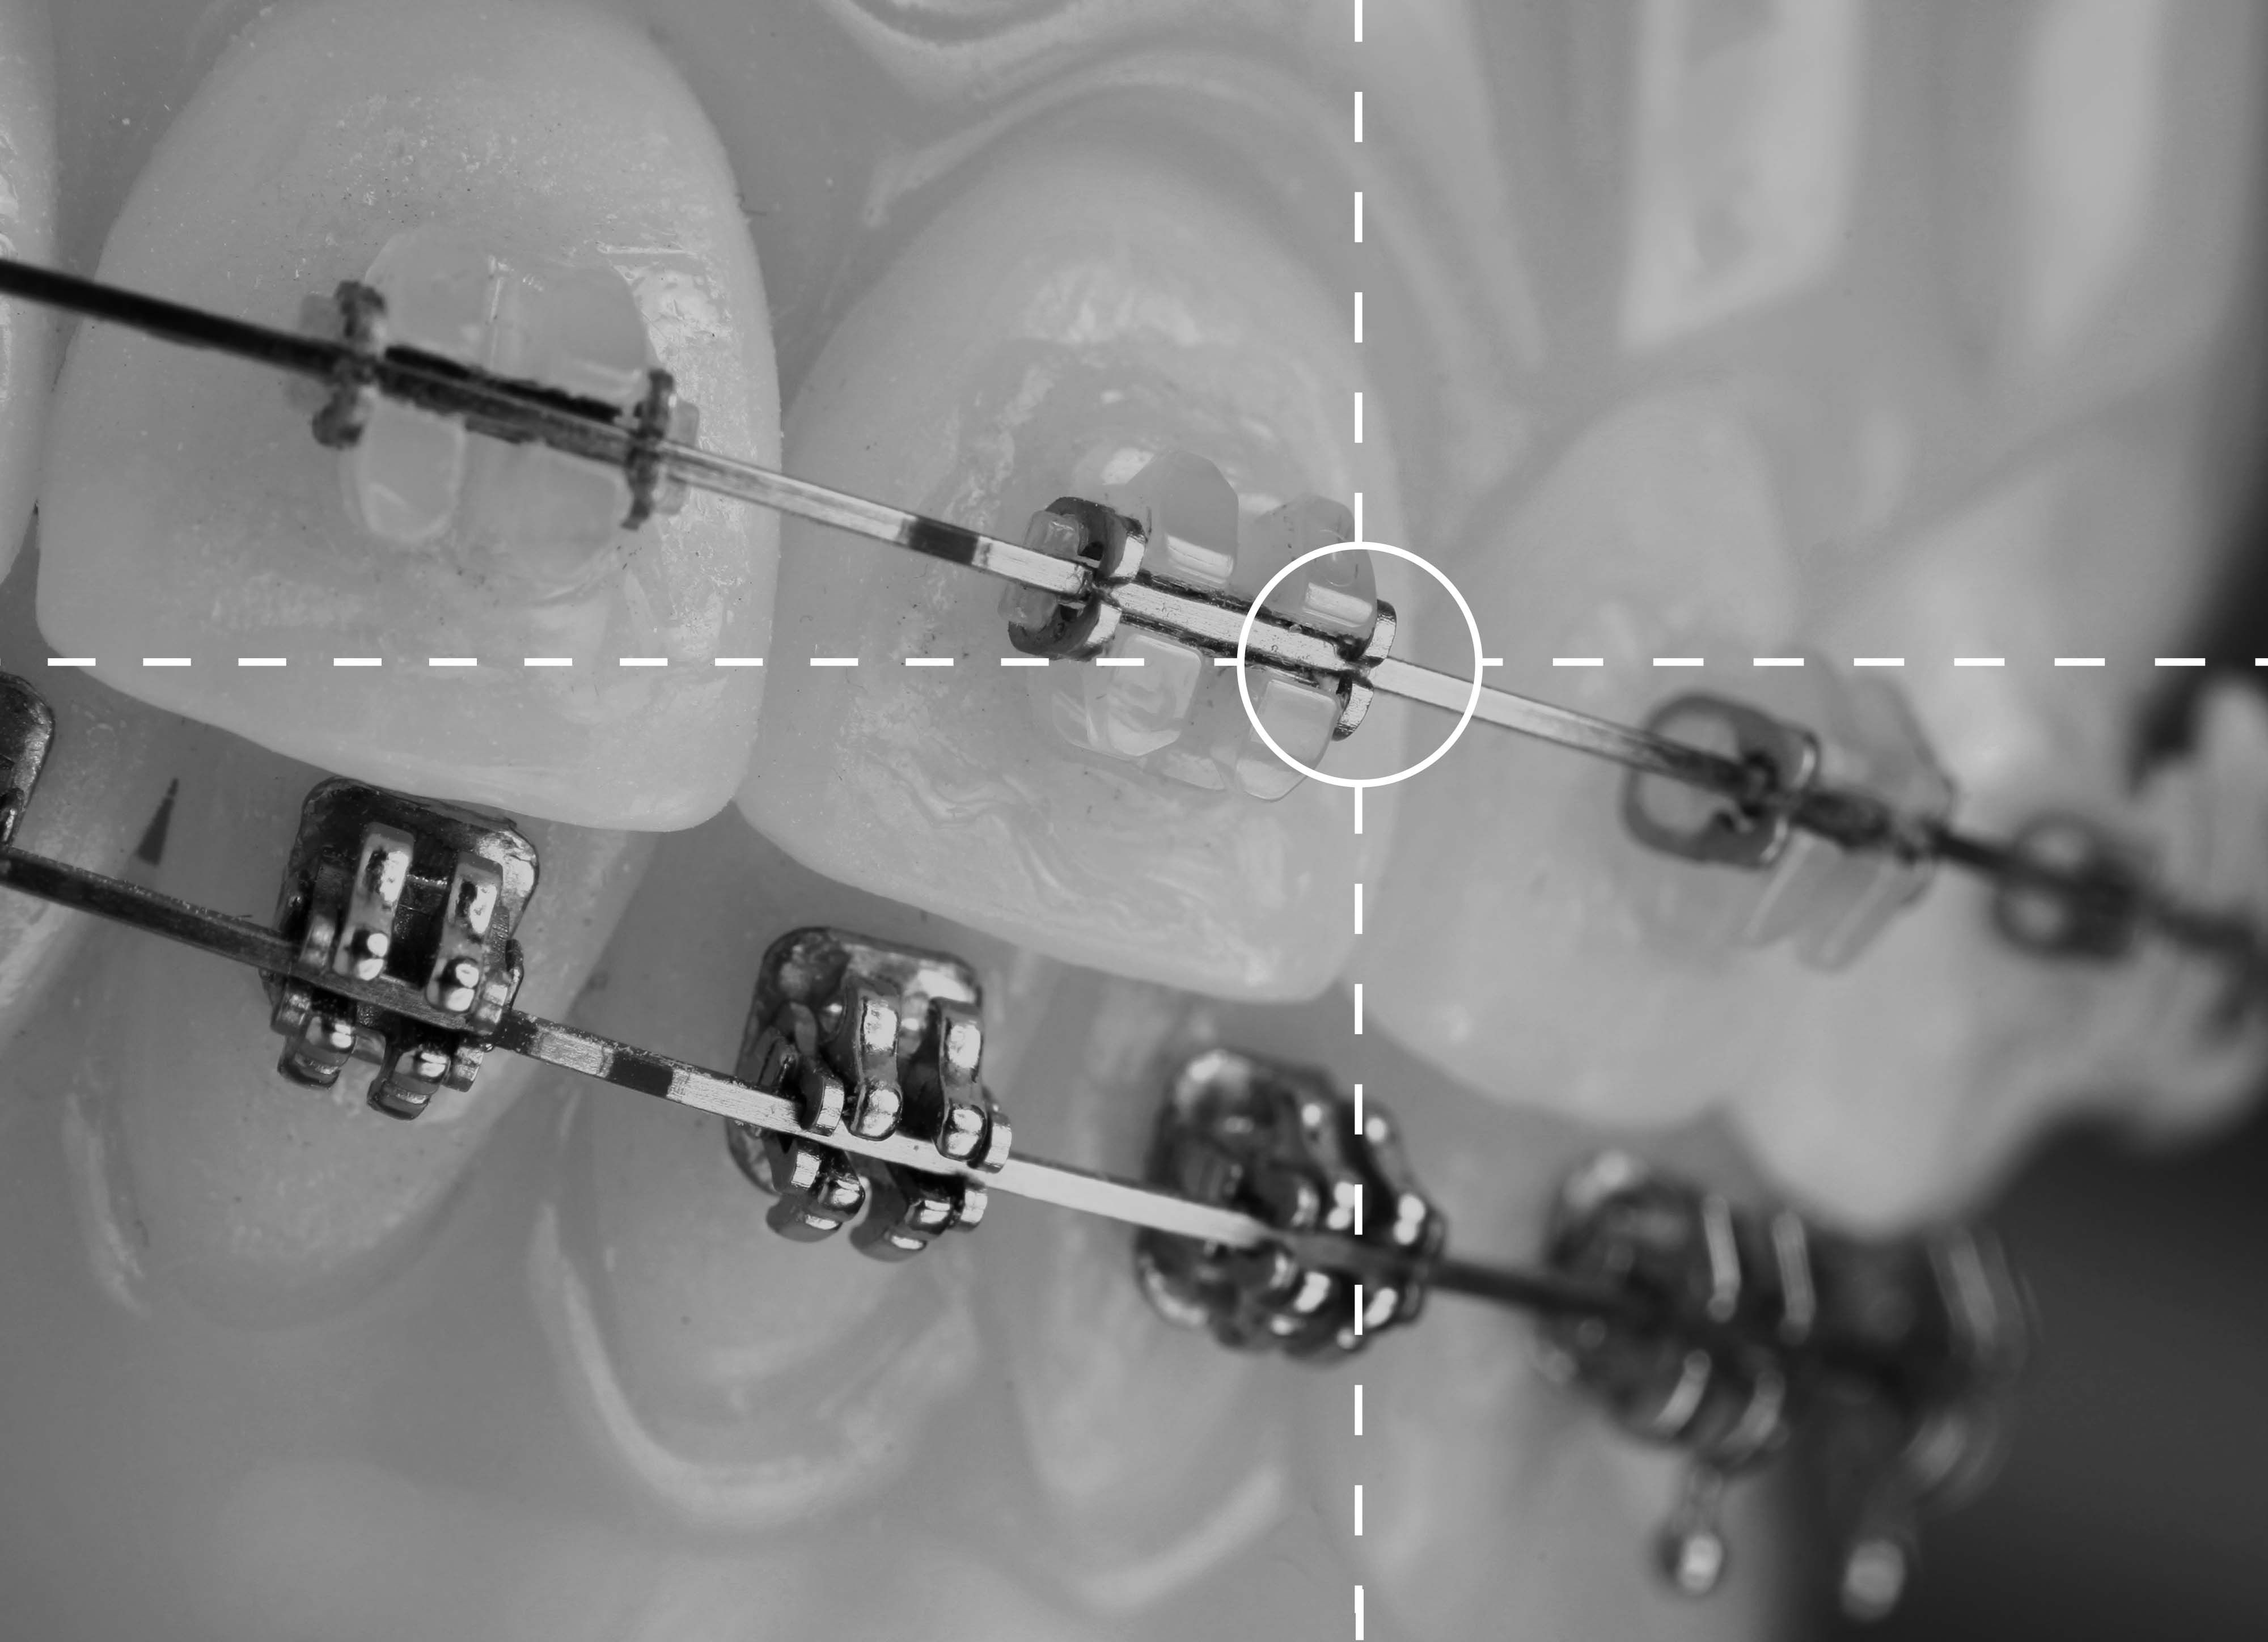

La periodoncia es una disciplina de la Odontología que se encarga del tratamiento de las enfermedades periodontales. Las más frecuentes son las gingivitis, que es la inflamación y sangrado de encías; y la periodontitis, pérdida de hueso, ligamento periodontal y cemento.

Su no tratamiento puede conllevar a la pérdida de la pieza dental.

En Clínica Dental Aizcorbe realizamos tanto tratamientos quirúrgicos como conservadores de enfermedades periodontales.